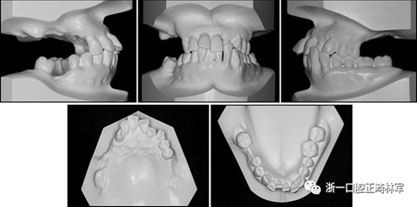

一名因多顆牙齒缺失和牙周損傷的49歲婦女被牙周科送往國民健康保險服務(wù)一山醫(yī)院的正畸科進行跨學(xué)科綜合治療。多顆后牙已在10天前被拔除。她的主訴是前牙列擁擠,她想改善美觀和功能。她的病史沒有提供有用信息,她沒有顳下頜關(guān)節(jié)紊亂的跡象。口外檢查顯示面部對稱,休息位時嘴唇不適,尖銳鼻唇溝和突出的嘴唇。她的下頜牙齒中線偏移到面部中線的左側(cè)(圖1)。

圖1. 治療前面部和口內(nèi)照片

口腔內(nèi)由于牙周炎,她的上頜右側(cè)第一和第二前磨牙,上頜右側(cè)第一和第二磨牙,上頜左側(cè)第一和第二磨牙以及下頜右側(cè)第一磨牙缺失。牙周探查顯示在磨牙區(qū)域和下頜骨左側(cè)側(cè)切牙區(qū)有深的牙周袋,還存在出血(表I)。上頜骨和下頜骨前牙擁擠,左側(cè)側(cè)切牙存在反合,下頜左側(cè)側(cè)切牙發(fā)過度萌出。覆蓋是5毫米,上頜切牙是唇傾的。在上頜弓中,尖牙和前磨牙是近中傾斜,右側(cè)尖牙過度萌出。而且,下頜右側(cè)第二磨牙向近中傾斜。尖牙處于I類關(guān)系,但無法評估磨牙關(guān)系(圖1和2)。

圖2. 治療前牙齒石膏模型